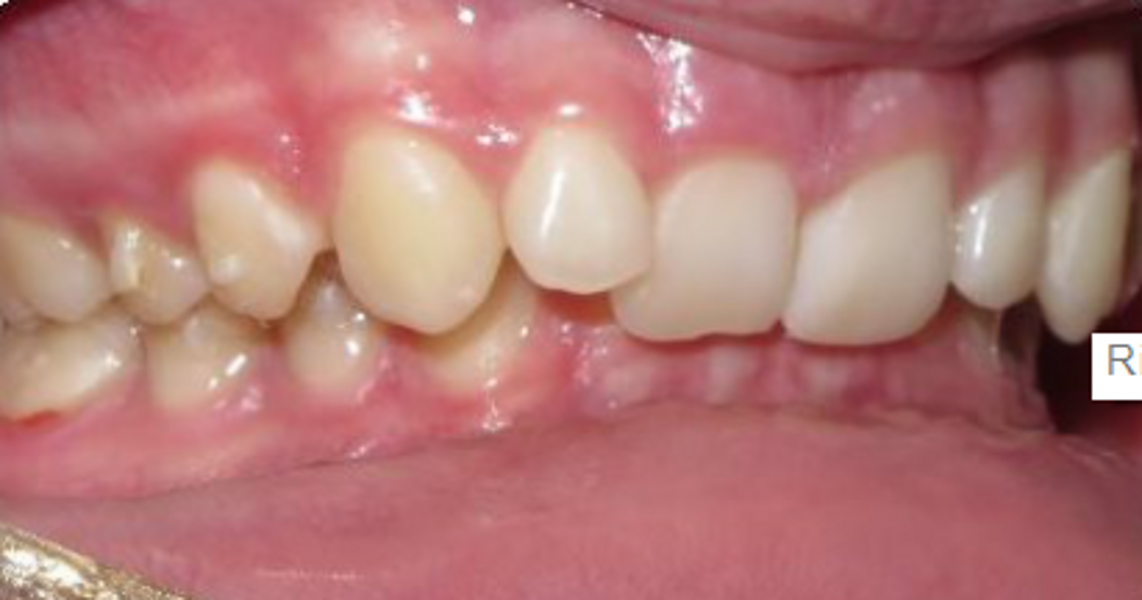

Fig. 18a: Class II malocclusion requiring fixed appliance treatment. (a) Lateral view. (b) Occlusal view.

Fig. 18b: Class II malocclusion requiring fixed appliance treatment. (a) Lateral view. (b) Occlusal view.